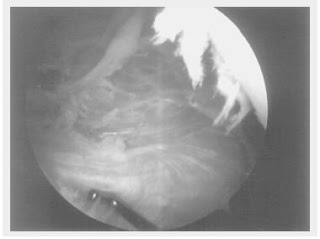

A sua visibilizaçào foi possível em todos os 5 joelhos estudados. (Figuras 6 e 7)

Figura 6 - Imagem obtida por visibilização artroscópica da região medial para patelar do joelho,pós sinovectomia, demonstrando o LFPM

Figura 7 - Imagem obtida por visibilização artroscópica da região medial para patelar do joelho,pós sinovectomia, com o gancho de palpação demonstrando o LFPM

Pudemos visibilizar, por transparência da membrana sinovial as fibras horizontais do ligamento dirigindo-se do bordo medial da patela até o epicôndilo medial.

Após a sinovectomia a visualização e a palpação do LFPM tornou-se evidente.

Trata-se de uma estrutura com aspecto tendinoso que dirige-se da face medial da patela até a região mais anterior do epicôndilo medial.